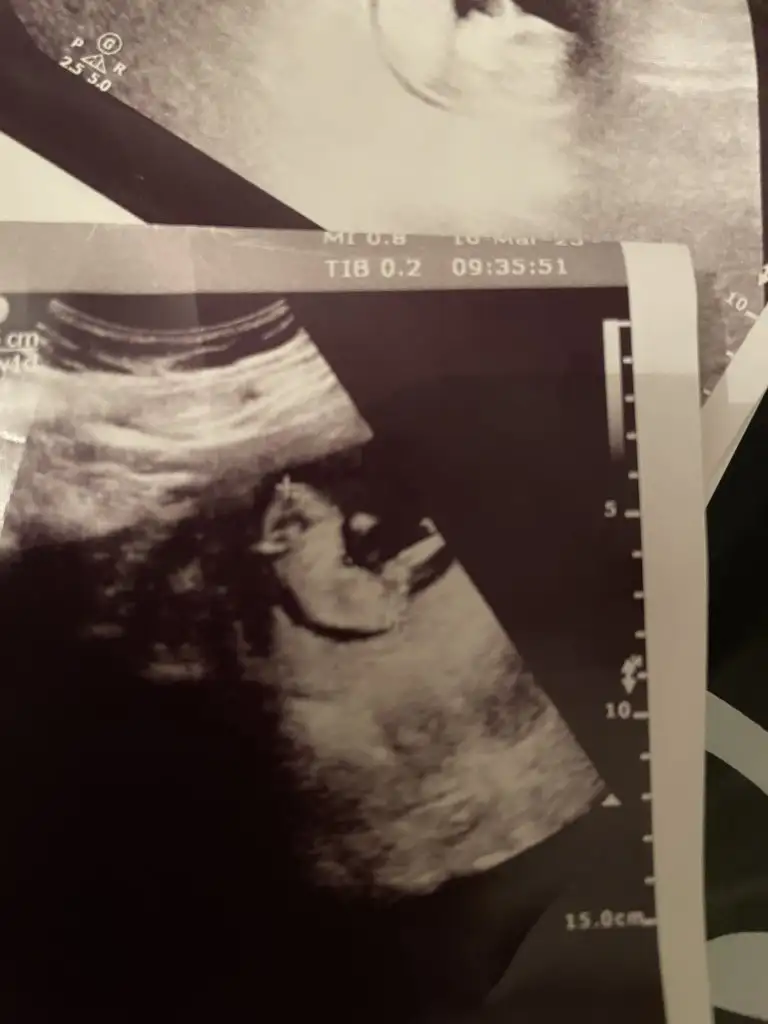

Sırayla 8-12-14 hafta hepsi karından yorumlarsanız sevinirim

12 haftalıkken erkege benziyor denildi 14 hafta kıza benziyor denildi 15 haftalık oldum hala bilmiyorum bebisimin cinsiyetini dahada doktora gitmeme 3 hafta var meraktan çatlamak üzereyim 😅